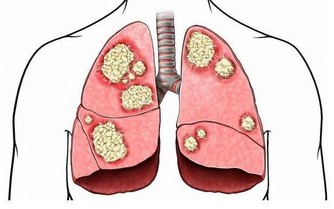

近年來癌症的發生逐漸年輕化,每年都有大量的年輕人被確診為癌症。很多腫瘤專科的大夫在臨床上深有體會,尤其是胃癌、肺癌、腸癌等常見癌症更是如此。

但是,消化道腫瘤發病的年輕化,一定是與飲食有很大的相關性。

飲食與癌症是密切相關的,這是值得肯定的。比如中醫也認為,過多地食用“膏粱厚味”,也就是油膩食物,會增加腸癌、胃癌、乳腺癌的發生率。油炸、熏制、醃製食物也會增加胃癌、食道癌等消化道癌症的發生機率。

長期的不健康飲食,尤其是長期食用油炸食物會增加患癌的風險,這絕不是危言聳聽。